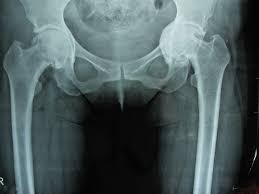

Η διάγνωση τίθεται από το ιστορικό, την κλινική εξέταση και μια απλή ακτινογραφία λεκάνης-ισχίου.

Η οστεοαρθρίτιδα του ισχίου είναι η πάθηση στην οποία παρατηρείται προοδευτική φθορά και καταστροφή της άρθρωσης. Οφείλεται στην εκφύλιση του αρθρικού χόνδρου αρχικά και του υποχόνδριου οστού σε προχωρημένο στάδιο.

Η πάθηση εκδηλώνεται αρχικά με πόνο κατά τη βάδιση αλλά και πόνο ηρεμίας (νυχτερινός πόνος) ενώ αργότερα υπάρχει χωλότητα και περιορισμός εύρους κίνησης με αποτέλεσμα ο ασθενής να δυσκολεύεται στην εκτέλεση απλών, καθημερινών ασχολιών όπως να ανέβει μια σκάλα ή ακόμα και να βάλει τις κάλτσες του ή τα παπούτσια του.